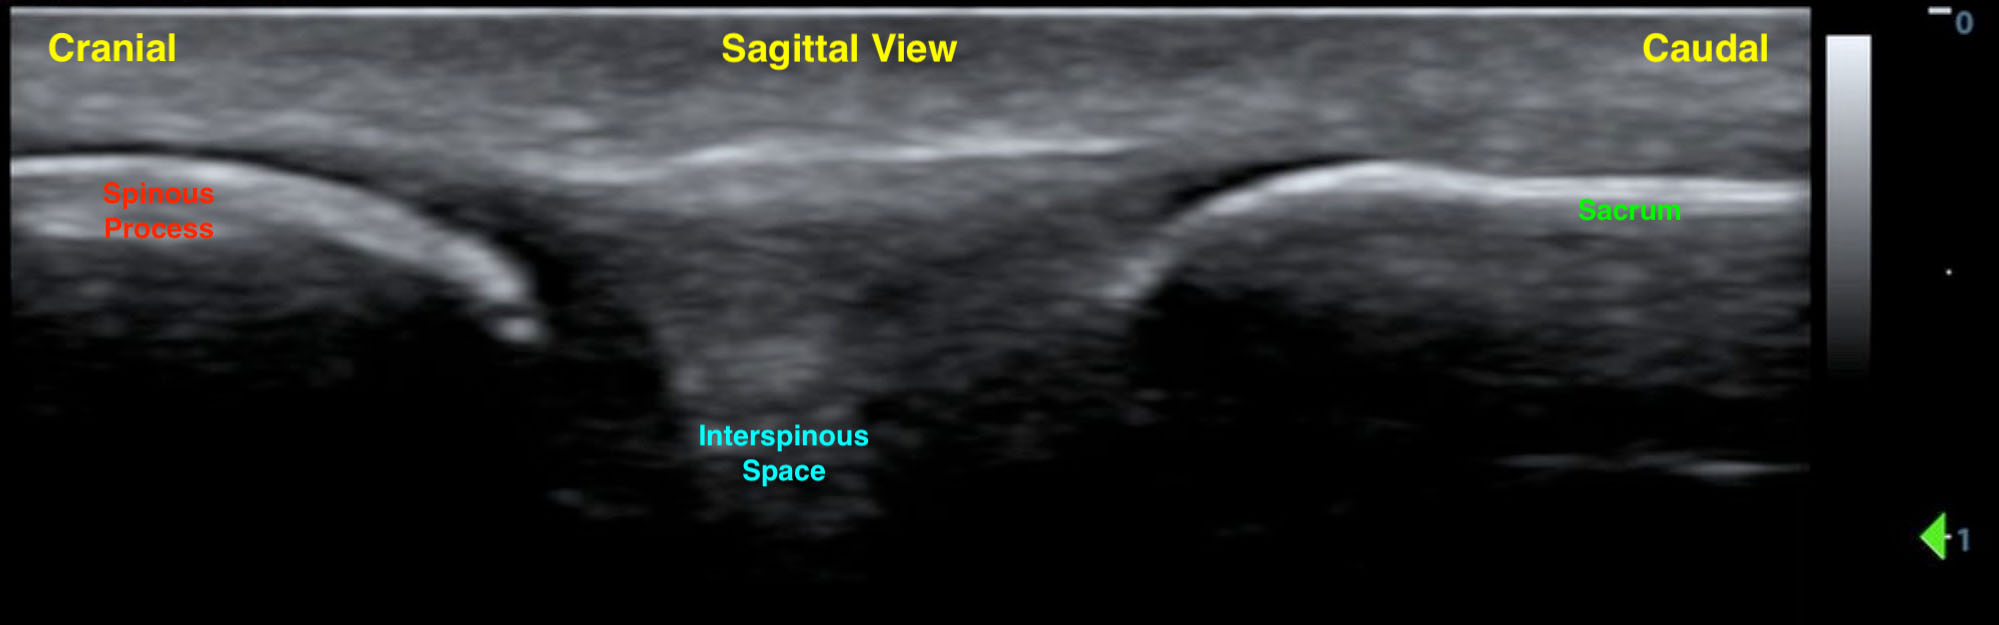

- Rotate the transducer to the sagittal plane to identify the sequential spinous process and the interspinous space. Scan caudally to identify the sacrum (a hyperechoic linear structure) (Fig. 3). This will allow you to count up from L5/S1 interspace to the L4/L5 and L3/L4 interspinous spaces.

- Figure 3. Sagittal spinous process and sacrum